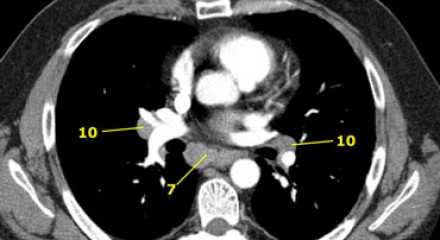

На ниже представленном постконтрастном КТ снимке представлен пациент с карциномой языка и лимфаденопатией II группы лимфатических узлов.

7. Подкаринальные лимфатические узлы

Эти лимфатические узлы расположены ниже уровня бифуркации трахеи (карины), но не относятся к нижнедолевым бронху и артерии. Справа они располагаются каудальнее нижней стенки промежуточного бронха. Слева они располагаются каудальнее верхней стенки нижнедолевого бронха. Слева лимфатический узел 7 группы справа от пищевода.

10. лимфатические узлы корня легкого

Лимфатические узлы корня расположены проксимальнее долевых узлов, но дистальнее медиастинальной дупликатуры и узлов промежуточного бронха справа.

Все лимфатические узлы 10-14 групп являются N1 узлами, так как они находятся вне средостения.